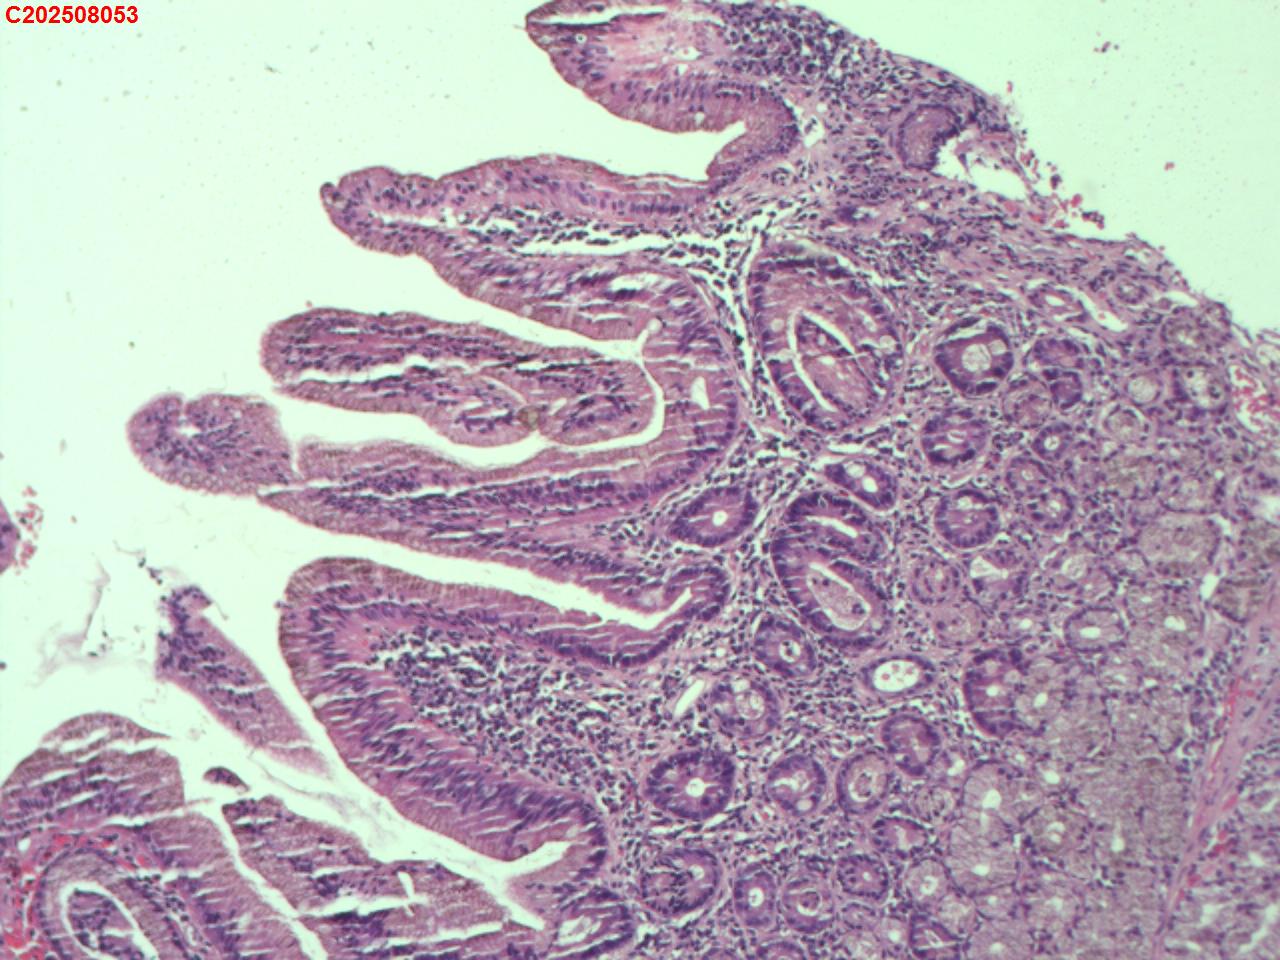

十二指肠黏膜

十二指肠球部息肉

十二指肠球部黏膜

十二指肠球部可见一息肉样隆起。

图3

增生性息肉。